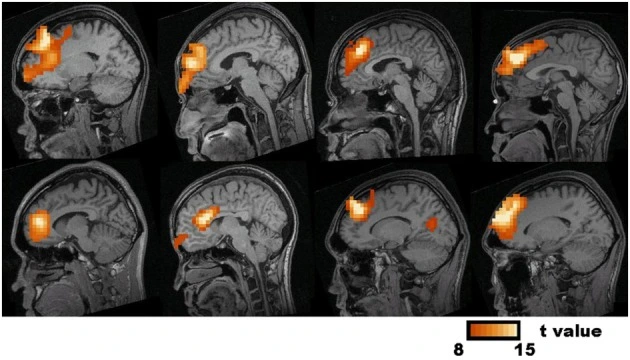

This is very cool. This is called "synthetic aperture magnetometry".

What they do here is combine the broad and diffuse EEG with an MEG "beam former" that precisely localizes current sources.

This is showing you the location of the frontal midline theta generator.

As you can see, it moves around.

The second brain image from the left, on the bottom, is especially interesting.

It's showing a source in the anterior cingulate cortex.

This proves that the focus of theta moves around quite considerably, not only within the frontal lobe, but even outside it, to areas that are connected with it yet distant.